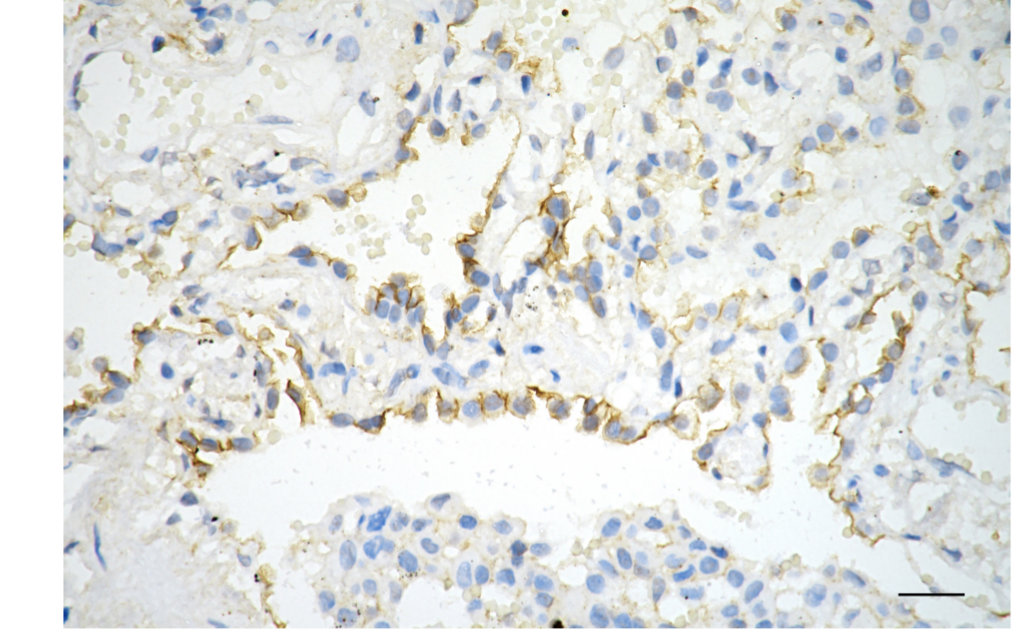

• Immunohistochemistry was performed on paraffin-embedded human lung adenocarcinoma using phospho-EGFR (Y1068) antibody. Antigen retrieval was done in sodium citrate buffer (pH 6.0). DAB was used for detection, with hematoxylin counterstaining. Images were acquired using a Nikon Ci-L Plus microscope (40× objective). Scale bar: 25 μm.